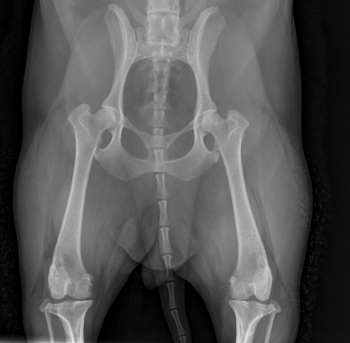

Badaniem można stwierdzić bolesność podczas biernych ruchów w stawie, mniejszy zakres ruchu w stawie, fenomen Ortolaniego – charakterystyczne „klikniecie” w stawie biodrowym wynikające z jego niestabilności. Najdokładniejszym badaniem jest badanie radiologiczne stawów biodrowych. Zdjęcie wykonuję się w projekcji grzbietowo-brzusznej – V-D, pies leży na grzbiecie (niekiedy konieczne jest wykonanie dodatkowych zdjęć w innych projekcjach). W większości przypadków do wykonania takiego zdjęcia konieczne jest uspokojenie pacjenta – sedacja i rozluźnienie mięśni – miorelaksacja, co uzyskuję się za pomocą iniekcyjnych środków farmakologicznych.

Objawy radiologiczne są różne w zależności od stopnia nasilenia zmian w stawie, dotyczyć mogą panewki stawu biodrowego, główki kości udowej lub obu struktur jednocześnie.